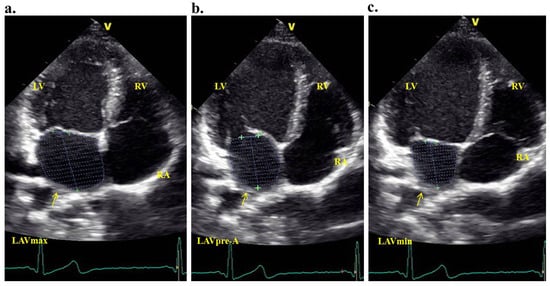

2.3. Assessment of Atrial Electromechanical Delay

Tissue Doppler echocardiography was performed using transducer frequencies ranging from 3.5 to 4.0 MHz, adjusting the filters of the spectral pulsed Doppler signal to achieve a Nyquist limit of 15 to 20 cm/s, and applying minimal optimal gain settings. In the apical four-chamber view, the pulsed Doppler sample volume was placed at the septal, lateral mitral annulus, and lateral tricuspid annulus locations. The atrial electromechanical connection (Pa’), defined as the time interval from the onset of the P wave on the surface electrocardiogram to the beginning of the late diastolic wave (a’), was captured from the lateral mitral (Pa’ lateral), septal mitral (Pa’ septal), and lateral tricuspid annuli (Pa’ tricuspid) (Figure 1a–c). The difference between Pa’ lateral and Pa’ tricuspid was termed as interatrial electromechanical delay, the difference between Pa’ lateral and Pa’ septal was defined as left intra-atrial electromechanical delay, and the difference between Pa’ septal and Pa’ tricuspid was defined as right intra-atrial electromechanical delay. The parameters were averaged over three sequential heartbeats.

Figure 1.

Atrial electromechanical coupling (Pa’), the time period from the beginning of the P-wave on the superficial electrocardiogram to the start of the late diastolic wave a’ on tissue Doppler echocardiography (mitral lateral annulus (a), septal annulus (b), and tricuspid lateral annulus (c)).